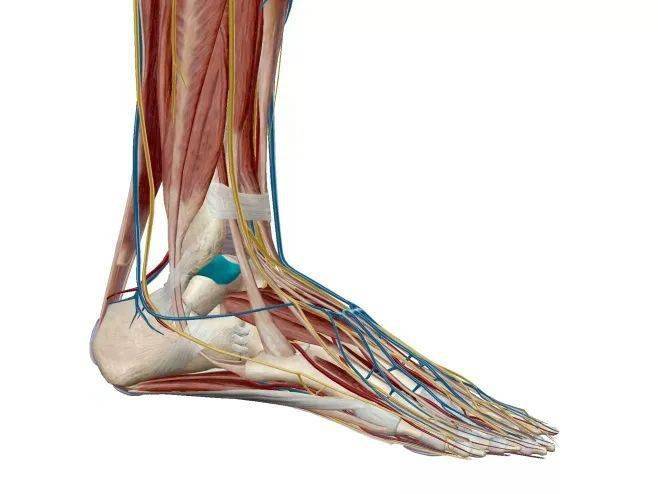

踝关节解剖分析

图片尺寸737x837